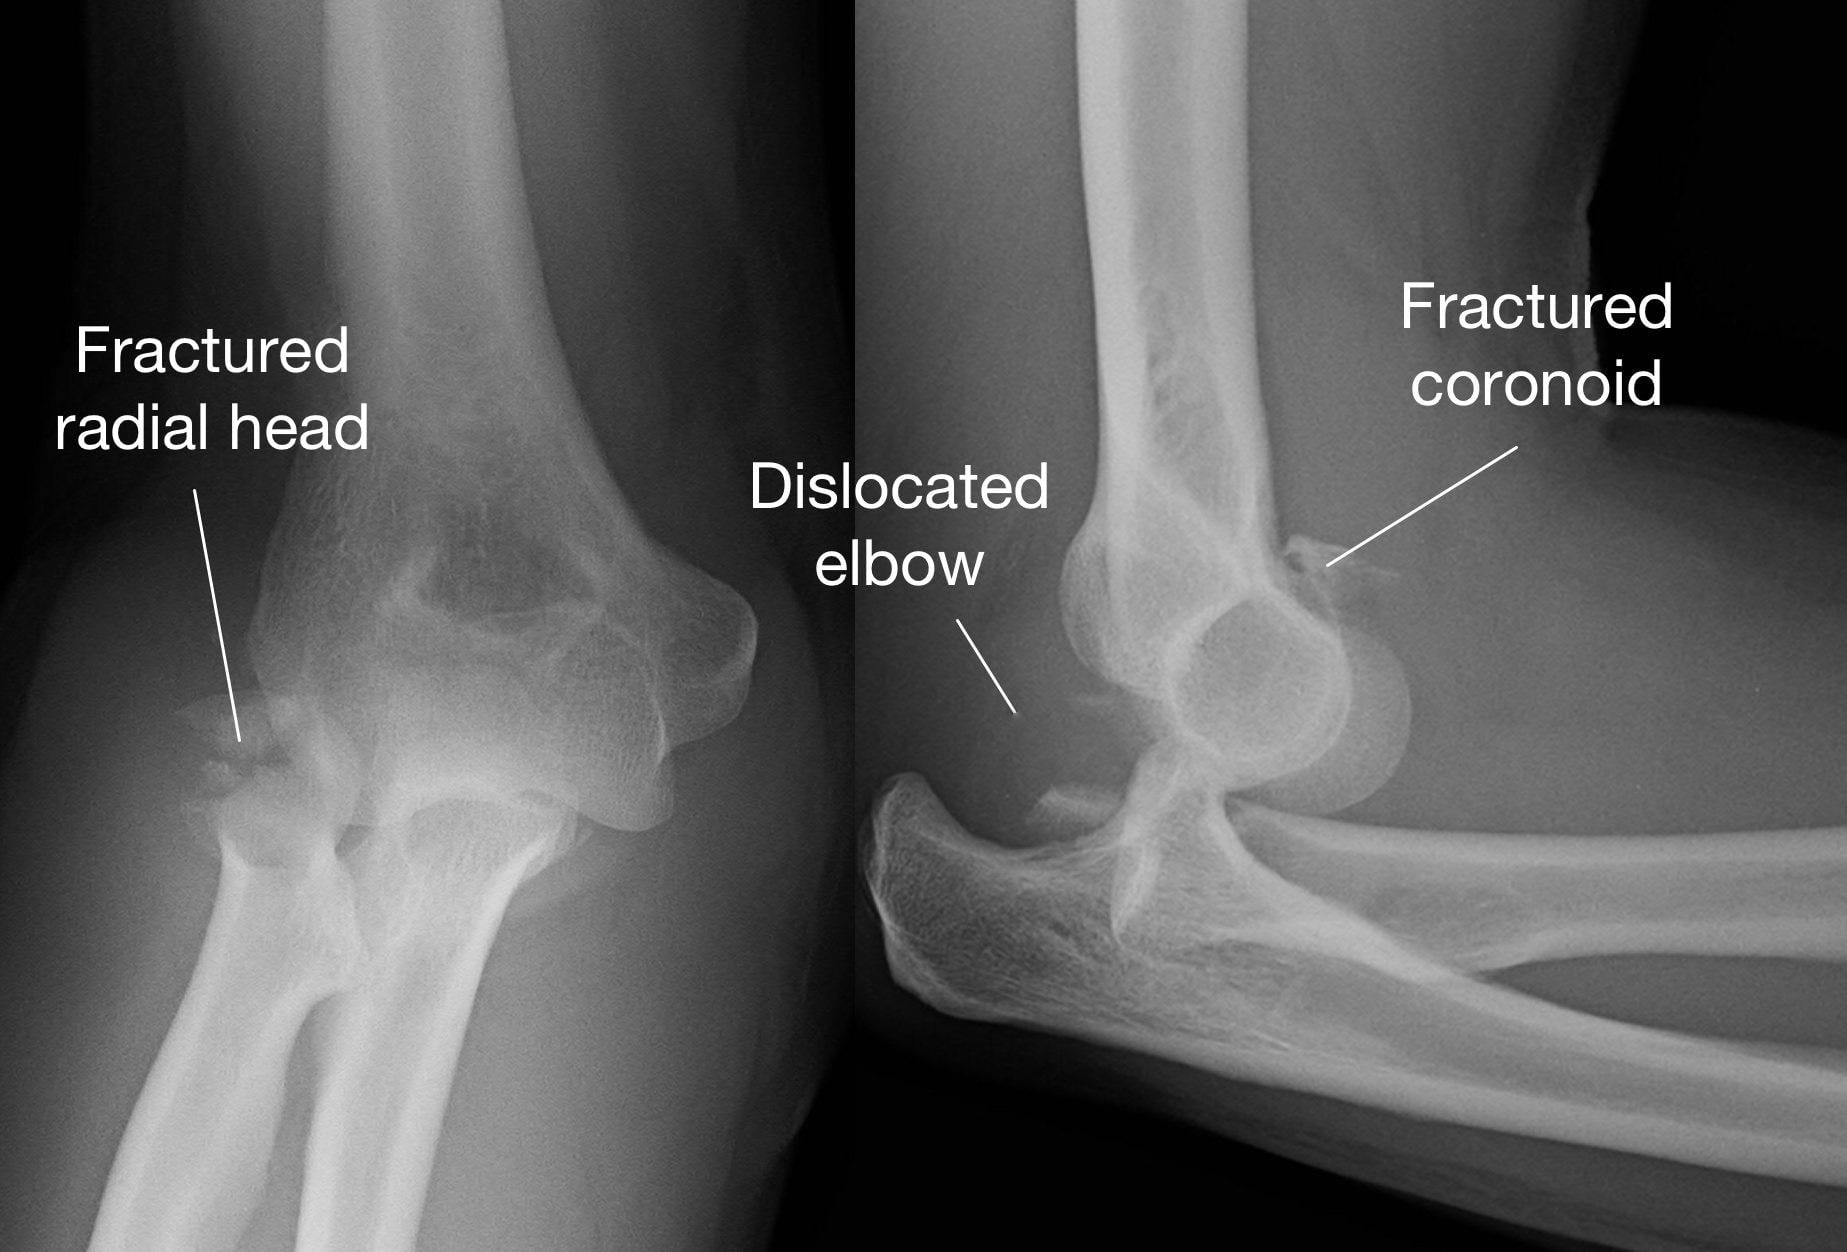

手肘脫臼恐怖三聯症是相當嚴重的情況,因為不只是手肘關節發生脫臼,關節旁邊的橈骨頭和尺骨冠狀突常是粉碎性骨折。

大里仁愛醫院骨科部長黃贊文醫生表示,手肘脫臼恐怖三聯症大部分發生在年輕人和中年人,主要是因為車禍或高處墜落等高能量撞擊所導致。手肘脫臼恐怖三聯症是相當嚴重的情況,因為不只是手肘關節發生脫臼,關節旁邊的橈骨頭和尺骨冠狀突常是粉碎性骨折。而最令骨科醫師感到棘手的是手肘關節的韌帶往往也斷裂,因此不只是將脫臼的手肘關節復位和固定好骨折,若不修補好韌帶,手肘關節依然不穩定而失去功能。

不只是將脫臼的手肘關節復位和固定好骨折,若不修補好韌帶,手肘關節依然不穩定而失去功能。